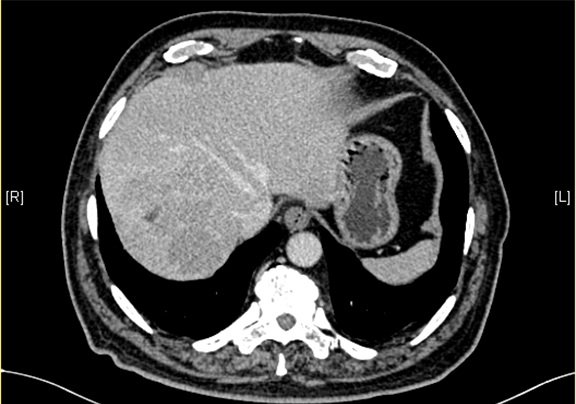

下腹部增强CT示:肝右后叶上段占位,肝癌可能性大;右侧肾上腺占位,不除外转移瘤。

术前CT检查:

动脉期

静脉期

平衡期